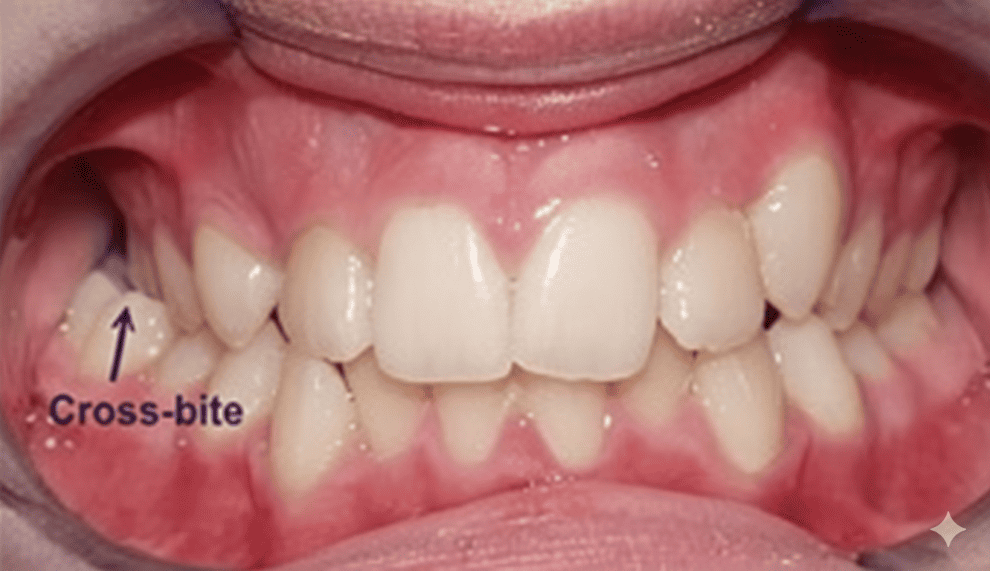

Posterior cross-bite

Case Study 2

Upper jaw growth → Corrected reverse bite

“Her lower jaw covering upper jaw, how can Dr help with this?”

Clinical observation

Treatment Outcomes

Her reverse bite was corrected in just a few months! 😁

Before (March 25)

After (Sep 25)